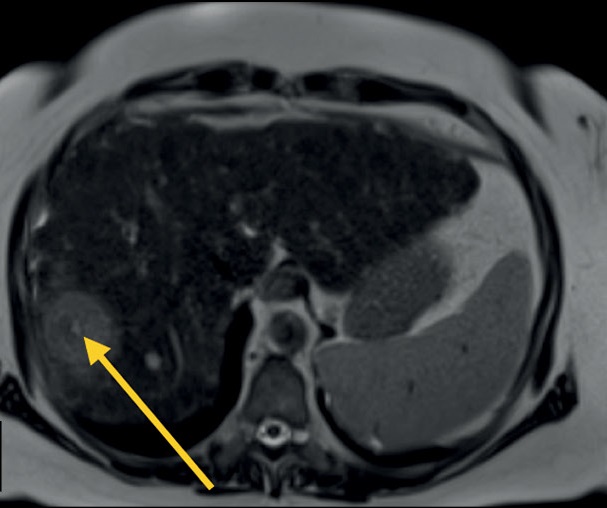

Basic pulse sequences in the diagnosis of abdominal pathology

Magnetic resonance imaging is used for diagnosing abdominal and retroperitoneal space pathology, which allows visualizing focal or diffuse lesions in the parenchymal and hollow viscera with high diagnostic accuracy and reproducibility. Magnetic resonance imaging has advantages over computed tomography in the sensitivity and specificity of determining pathological changes in parenchymal organs, bile ducts and ducts of the pancreas, peritoneum, and retroperitoneal space.

The multiparametric protocol provides information about the mutual topography of organs and their structure and the functional state of tissues. This allows to move from structural to functional evaluation. In most cases, the standard abdominal protocol includes T1-weighted images, T2-weighted images, diffusion-weighted images, and magnetic resonance cholangiopancreatography. Depending on the objectives and patient’s condition, this protocol can be significantly reduced or supplemented.